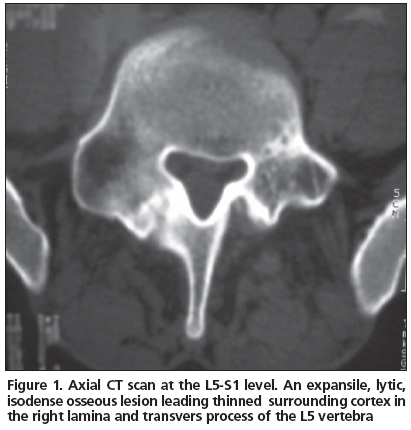

A 21 year-old male patient admitted to our clinic with low back pain persistent to medication for the last 3 years. He was first referred to physical medicine and rehabilitation department and then to a neurosurgery department after several visits because of persistent pain. He had no history of trauma. His pain was not aggravated by coughing, standing or sitting; and the pain was not relieved by salicylates or NSAIDs. Whole blood count (CBC), erythrocyte sedimentation rate (ESR) and rheumatoid factor (RF) were found within normal limits. Physical examinations were found normal except the tenderness extending from T12 to L5 associated with paravertebral muscle spasm. His lumbosacral CT was taken and then a tumoral mass was noticed enlarging transverse process and right lamina of L5 vertebrae with probable diagnosis of osteoblastoma or osteoid osteoma. The mass had a lytic nature with well defined osteosclerotic boundaries and facet joints were normal (Figure 1). An MRI was taken to evaluate the soft tissue expansion which showed no affection (Figure 2). A CT-guided biopsy resulted with unsatisfactory sample gathering. Then he has taken to the operation theatre and curettage and frozen section was performed since the probable diagnosis was osteoblastoma. After confirmation of benign tumoral process, the cavity was filled with allograft. The histopathological examination confirmed the diagnosis of osteoblastoma. Following surgery, the patient was asymptomatic; there was no neurological dysfunction and no residual pain or discomfort. No recurrence has been observed for four years.

Osteoblastomas are composed of an abundantly vascular connective-tissue stroma with active production of osteoid and primitive woven bone. A central lucency with a variable zone of peripheral sclerosis is the typical pattern; osteolysis and mass effect are frequently present[3]. It can be seen in any area of skeleton but it is the only benign tumor which shows primary affection to spinal column, and both the body and posterior arch of vertebrae[3,5]. The diagnostic radiographic feature is usually a single, round area of osteolysis which expands the bone and it is not always with well defined boundaries. Marked osteolysis may be seen around the lesion which is not as extensive as in osteoid osteoma[6]. Histologically, osteoid osteomas and osteoblastomas are similar. Their most remarkable difference is: osteoblastoma has an unlimited growth potential with a capability of malignant transformation and is larger in size (usually larger than 2 cm). Plain radiography and CT findings are similar, including radiolucent nidus, matrix calcifications, and accompanying bony sclerosis. Differentiation is made on the basis of size, and the larger lesions are typically categorized as osteoblastoma, but osteoblastoma detected early and not exceeding a diameter of 2 cm makes the distinction difficult. Then, clinical presentation plays an important role in the diagnosis. Osteoblastomas are known to have a high incidence of neurological deficit. Neurologic involvement has been reported in 25–50% of patients. The tumor located in the spine can cause neurological symptoms. The case presented here had no neurological deficit.